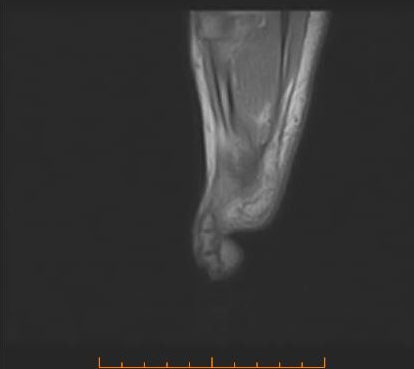

RISONANZA MAGNETICA DEL PIEDE - PIEDE SAGGITALE

La Risonanza Magnetica del piede (RM piede) è un esame non invasivo che ci permette di evidenziare i tessuti molli del piede (muscoli, tendini, legamenti) che non si possono apprezzare con la tradizionale radiografia. Se da una radiografia eseguita non si evincono patologie a carico dell’osso, la risonanza magnetica può essere utile come esame di…